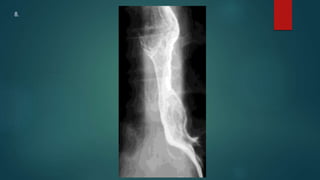

This document appears to be a medical report discussing several patients. It mentions a 35-year-old who was in a severe motor vehicle accident and an 81-year-old with a history of a non-vegetarian diet who had a perforated bowel from a chicken bone. The document provides few other details across its 25 numbered entries and was authored by Dr. Anish Choudhary for junior year 3 on May 30, 2016.